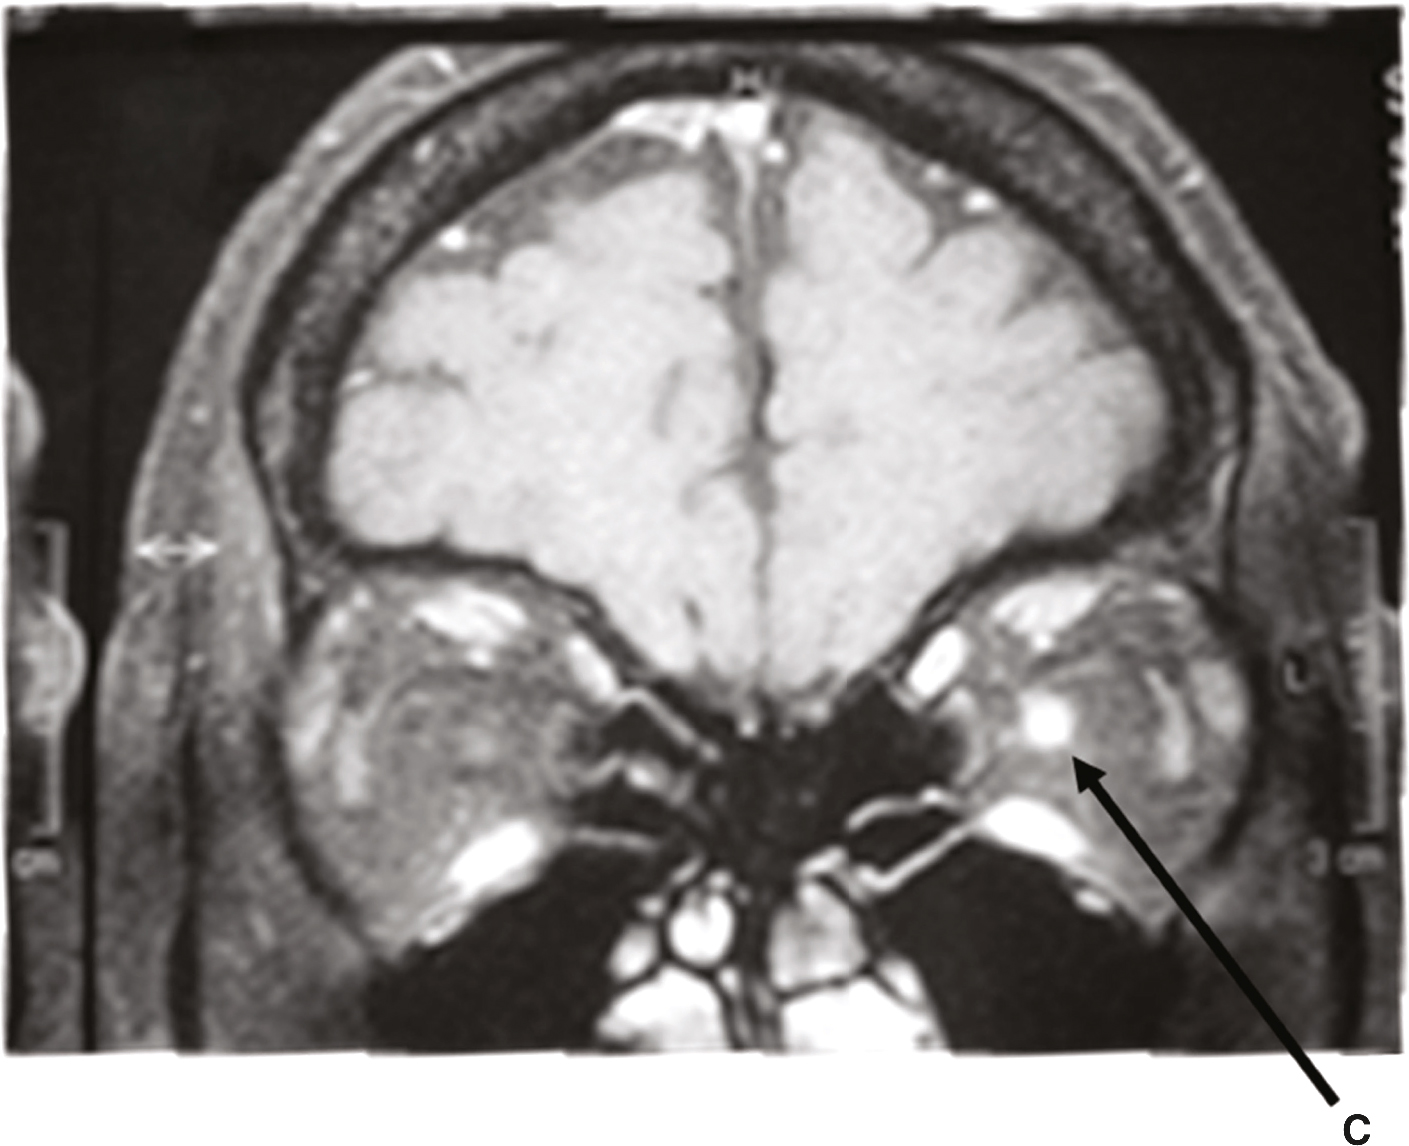

Fig. 15.2

IRM cérébrale et orbitaire en coupe coronale T1 avec injection de gadolinium. Hypersignal du nerf optique gauche.L'image montre une IRM cérébrale et orbitaire en coupe coronale T1 avec injection de gadolinium, une technique d'imagerie médicale utilisée pour obtenir des images détaillées du cerveau et des orbites (les cavités contenant les yeux). L'injection de gadolinium, un agent de contraste, permet de mieux visualiser certaines structures et anomalies en augmentant le contraste des images. Sur cette image spécifique, on observe un hypersignal du nerf optique gauche, ce qui signifie que cette région apparaît plus brillante sur l'image. Cet hypersignal peut indiquer une inflammation, une lésion ou une autre anomalie du nerf optique. Le nerf optique est crucial pour la vision, car il transmet les informations visuelles de l'œil au cerveau. Une anomalie dans cette région peut donc avoir des conséquences importantes sur la vision. La flèche rouge sur l'image pointe directement vers le nerf optique gauche, soulignant l'endroit précis de l'hypersignal. Cette observation est essentielle pour diagnostiquer et comprendre les anomalies affectant le nerf optique et leur impact potentiel sur la vision du patient. En résumé, l'IRM montre un hypersignal du nerf optique gauche, signalant une possible anomalie dans cette région.